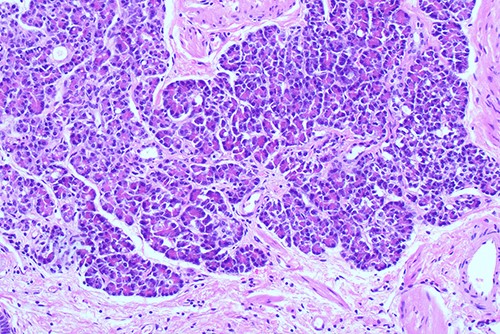

Histological examination of gallbladder ×40 showing island of ectopic pancreatic tissue adjacent to the mucosa of the gallbladder neck.

Histological examination ×100 showing ectopic tissue consisting of pancreatic acini and small ducts. No islets are seen.